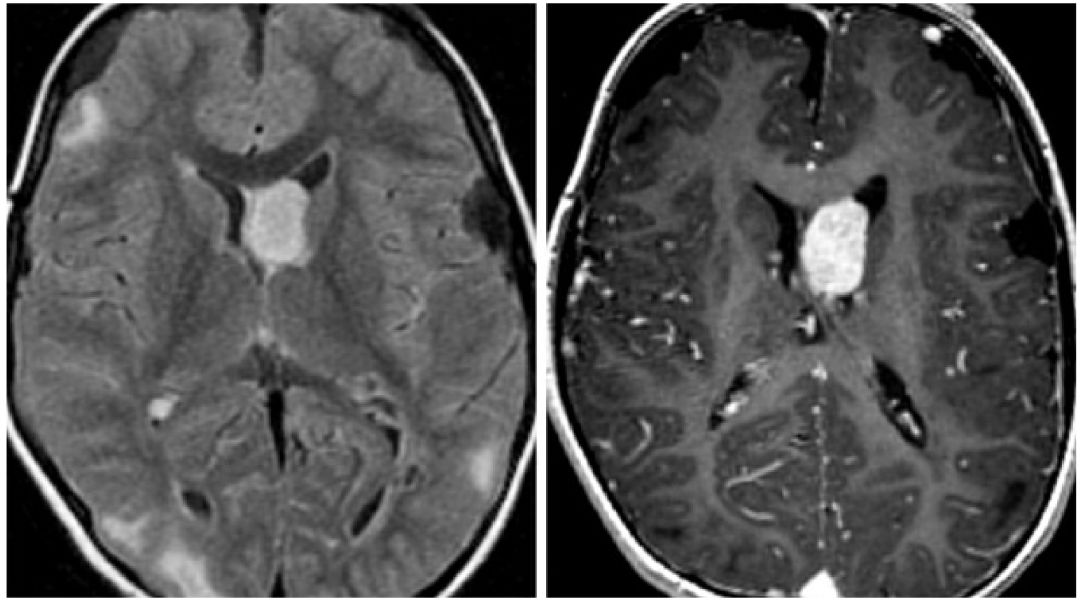

图1. 室管膜下巨细胞型星形细胞瘤(SEGA)的典型好发位置为室间孔附近,在结节性硬化症患者,肿瘤体积大于可见的室管膜下结节。左图:FLAIR相上可见多发的皮层下高信号团块影,位于脑室内室管膜下的肿瘤也呈高信号改变,其余的钙化室管膜下结节不明显;右图:T1增强加权像上可见典型的SEGA强化改变。

(3)FLAIR加权相:混杂高信号,急性脑积水和脑脊液渗入继发的室周高信号

(5)T1加权增强相:明显强化